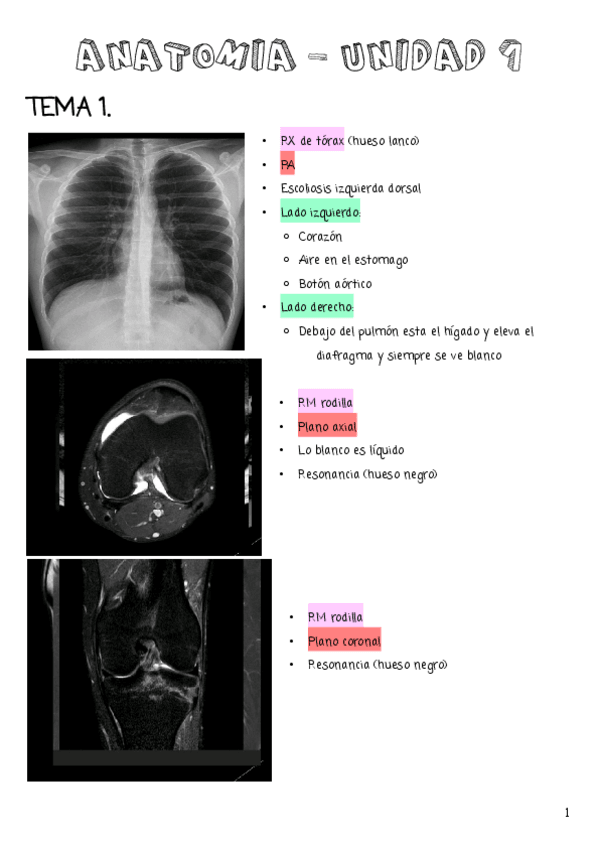

Apuntes - UNIDAD-7.pdf

23